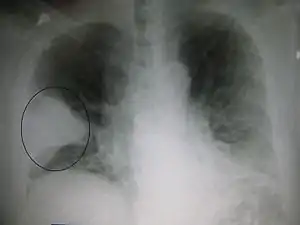

Right upper lobe pneumonia as marked by the circle.